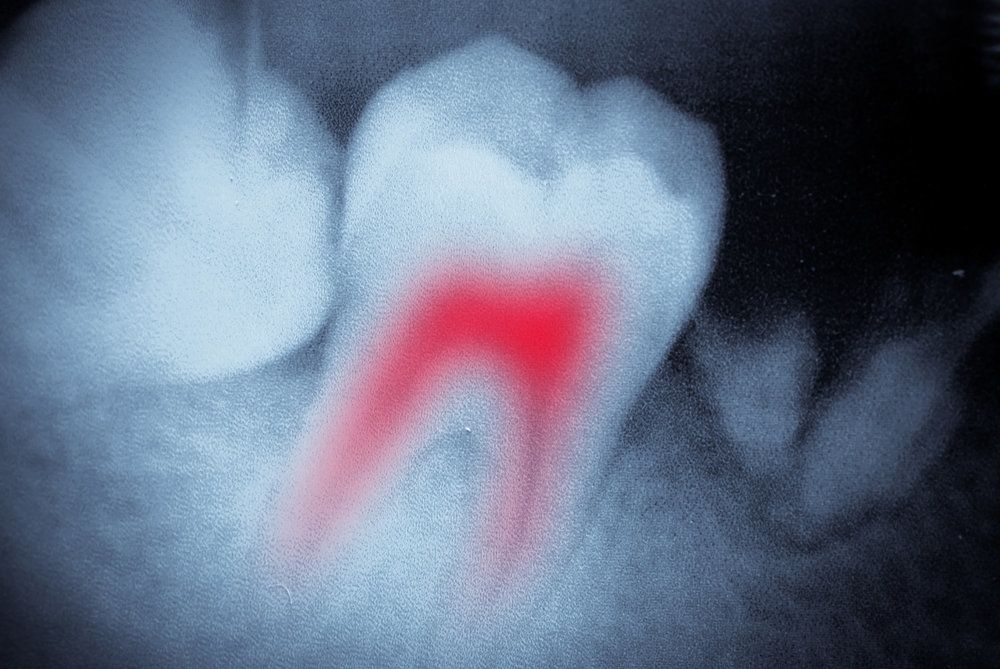

Root Canal Therapy

A deep chip, crack, or cavity can compromise the health of a tooth’s root, and once the root becomes infected, it will die and lead to a cascade of related oral health issues. A dentist may suggest root canal therapy for a tooth with internal infection. If you have a chronic toothache or have been told that you need a root canal, but you would like a second opinion, schedule an evaluation with us. With today's modern dental techniques, root canal therapy is often compared to the sensation of receiving a filling, so you can expect to remain comfortable during and after your treatment.